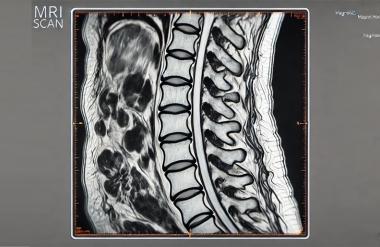

В 2026 году жители Санкт-Петербурга могут пройти МРТ пояснично-крестцового отдела позвоночника бесплатно – по полису обязательного медицинского страхования.

Первое, что требуется для прохождения бесплатной МРТ, – это направление от врача государственной поликлиники. Направление выдается только при наличии объективных показаний: стойкий болевой синдром, неэффективность терапии, подозрение на компрессию корешков, грыжи межпозвонковых дисков и другие неврологические проявления. По инициативе пациента, без чёткой клинической картины, направление выдано не будет.